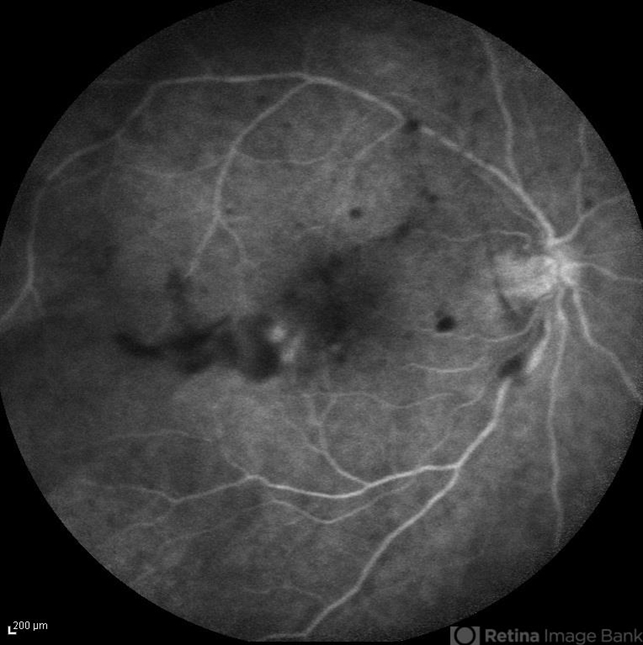

- candida endophthalmitis, endogenous endophthalmitis

- Late phase FA image of the right eye of a 45-year-old diabetic man with the history of urinary tract infection. The most probable diagnosis was candida endogenous endophthalmitis.